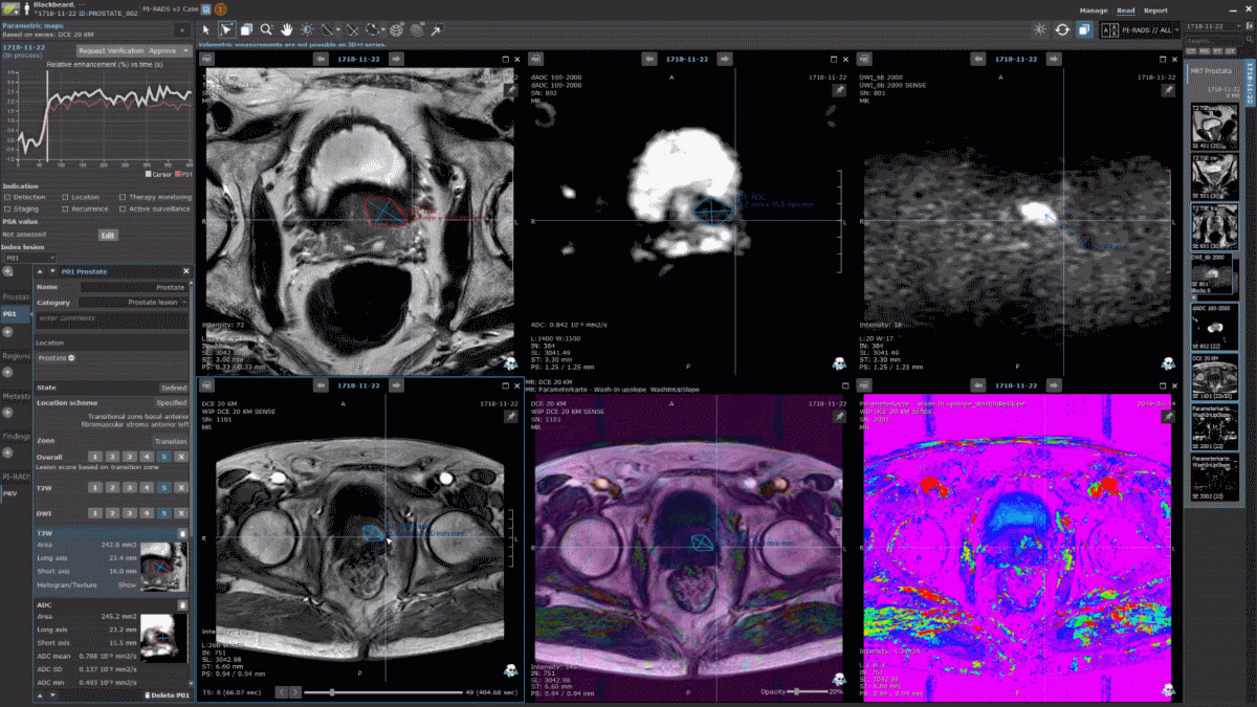

In an often time-consuming multi-parametric prostate MRI read, for instance, mint Lesion™ can automatically import clinical context information into a dedicated and customizable reading profile for the particular job-to-be-done. The clinical data includes PSA values from laboratory reports. These are automatically combined with the volumes of the prostate obtained from the MRI to determine the PSA density. Furthermore, with mint Lesion™ 3.5, measurements of a lesion can be copied to other image series, as the DWI or DCE MRI data. mint Lesion™ also assists in classifying the PI-RADS score of the lesion, and it automatically derives the overall score and index lesion. The resulting report comes in a structured form and includes visualizations and diagrams for reproducibility by referrals. The results can be forwarded as DICOM objects to the urologist and be used as basis for a more precise biopsy. Researchers may correlate the MRI-based results with biopsy information and data from pathological reports by means of mint Analytics. It allows to visually explore interdisciplinary, structured data to achieve advances in the value of image-based diagnostics.

Overall, mint Lesion 3.5 involves AI over the various steps of the radiological read: Beginning with an understanding of the clinical context of the particular patient case to the automatic generation of structured, reproducible reports. Hence, with the help of AI, tomorrow's radiologists will make decisions having their patient's disease data and reports precise and focused. Learn more about mint Lesion 3.5, contact us.